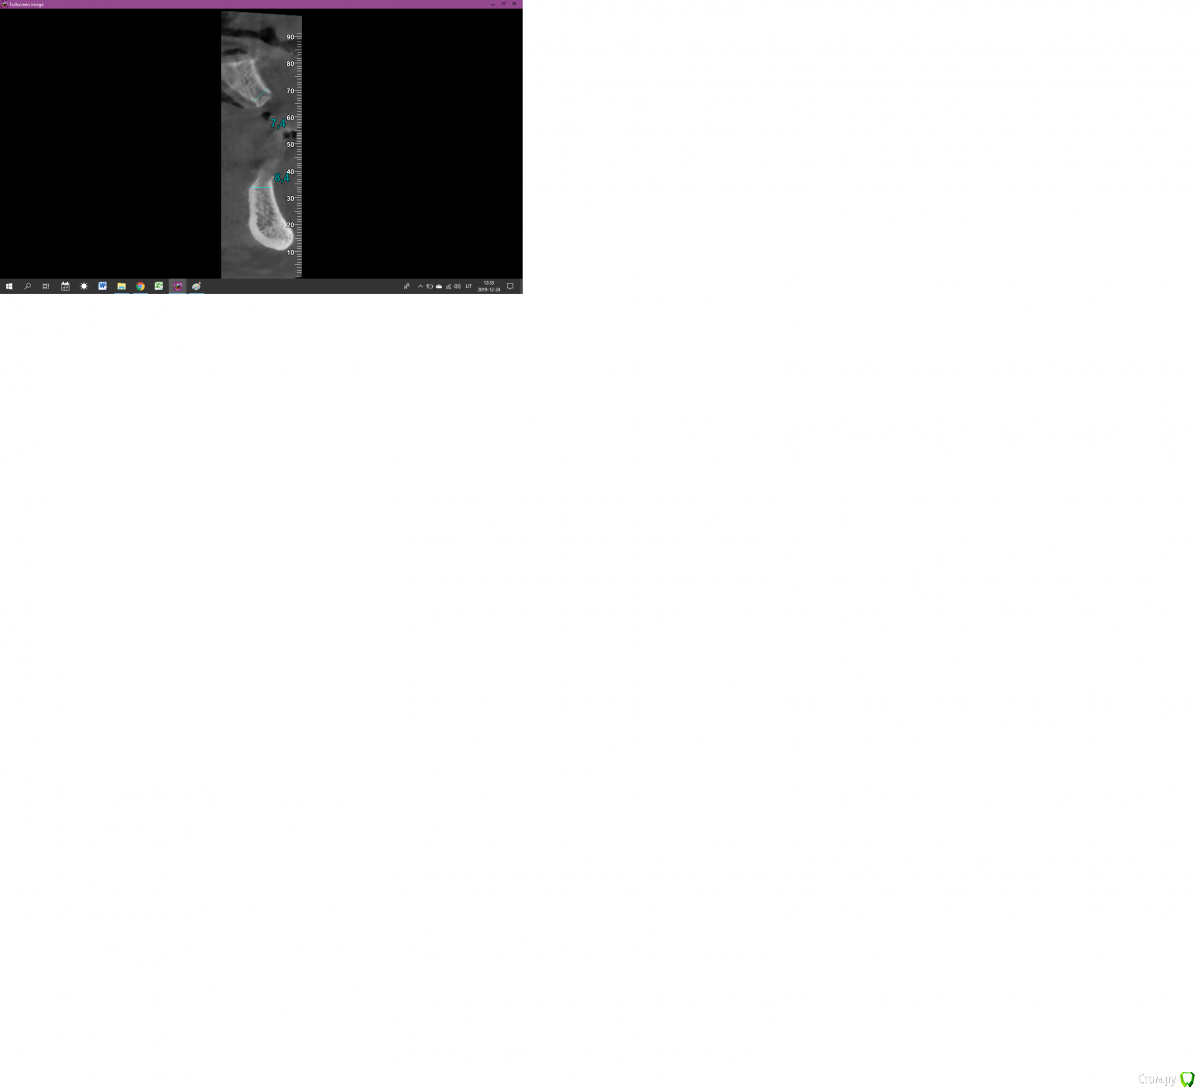

Lostikas Опубликовано 24 декабря, 2019 Поделиться Опубликовано 24 декабря, 2019 (изменено) Всех с наступающими праздниками! Коллеги прошу помогите разобраться с планом лечения. Полная реабилитация рта на имплантах, вопрос по поводу в/ч Возможно ли провести не большой закрытый синус лифт в области 15 зуба(1-2мм) и 25 зуба (1-2мм) при данном состоянии пазух особенно левой. лифт на сгустке без графта. если нет тогда план такой?: 4 импланта боковые под углом(класический ол он 4) далее к лору привести в порядок пазухи и через пару месяцев добавит в обости15-16 и 25-26? Спасибо! 2 фото область 25 зуба3 фото 15 Изменено 24 декабря, 2019 пользователем Lostikas Ссылка на комментарий

Bier Опубликовано 26 декабря, 2019 Поделиться Опубликовано 26 декабря, 2019 Олег а как бы вы поступили в данной клинической ситуации? справа там 8мм, слева 10? Поставил бы без синуса туда TL Ссылка на комментарий